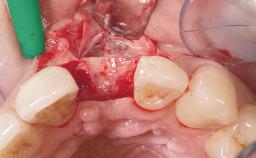

This 43-year-old male patient, a non-smoker, came to our practice because of a fracture of tooth 12 caused by a bicycle accident. Due to the combined para- and infrabony crown and root fracture, tooth extraction, and subsequent implant placement were suggested to the patient as the therapy of choice. The patient had high esthetic expectations with regard to the treatment outcome and asked for an immediate fixed provisional restoration. His individual esthetic risk profile summed up to a medium esthetic risk.